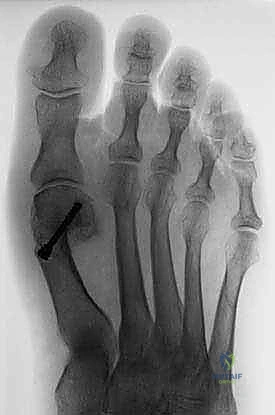

2. التقييم الشعاعي (Radiographic Evaluation)

تعتبر الأشعة السينية (X-rays) حجر الزاوية في التخطيط لعملية شيفرون البعيدة. يطلب الدكتور هطيف صور أشعة بوضعيات محددة (أمامية خلفية، وجانبية) أثناء وقوف المريض وتحميل وزن جسمه على قدميه (Weight-bearing X-rays). هذا أمر بالغ الأهمية لأن التشوه يظهر بحجمه الحقيقي فقط تحت تأثير وزن الجسم.

من خلال هذه الصور، يقوم الدكتور هطيف بقياس زوايا حاسمة تحدد نوع الجراحة المطلوبة:

* زاوية إبهام القدم الأروح (Hallux Valgus Angle - HVA): هي الزاوية بين المحور الطولي لعظم المشط الأول والمحور الطولي للسلامية الدانية. الزاوية الطبيعية أقل من 15 درجة. في الحالات الخفيفة إلى المتوسطة (التي تناسبها عملية شيفرون)، تتراوح بين 15 إلى 40 درجة.

* الزاوية بين أمشاط القدم (Intermetatarsal Angle - IMA): هي الزاوية بين المحور الطولي لعظم المشط الأول وعظم المشط الثاني. الزاوية الطبيعية أقل من 9 درجات. عملية شيفرون البعيدة مثالية عندما تكون هذه الزاوية بين 9 و 15 درجة.

* تقييم مفصل (DMAA - Distal Metatarsal Articular Angle): لتقييم ميلان السطح المفصلي.

* موقع العظام السمسمية: تقييم مدى انزياحها عن مسارها الطبيعي.

* وجود التهاب مفاصل تنكسي (خشونة): فحص تآكل الغضاريف، حيث أن وجود خشونة شديدة قد يغير خطة العلاج من عملية شيفرون إلى عملية دمج المفصل (Arthrodesis).